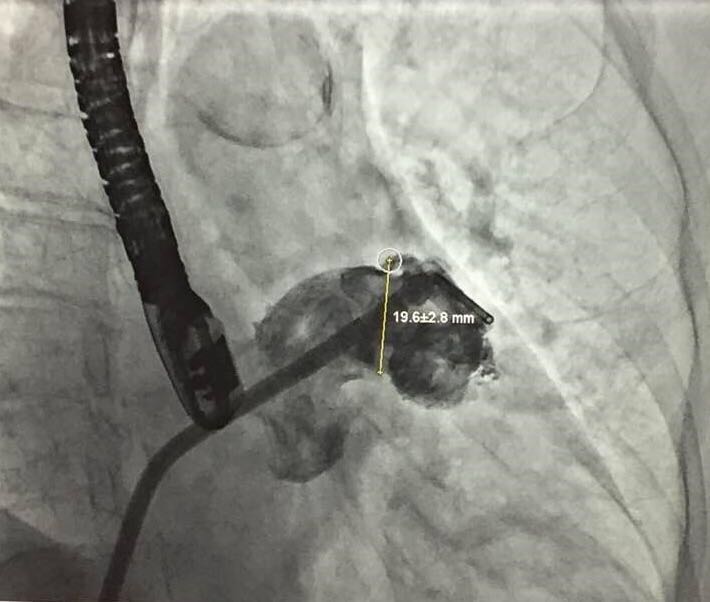

患者左心耳测量结果——锚定区

当日接受手术的患者为一名74岁女性,伴有高血压,脑卒中,心律失常。入院评估CHA2DS2-VASc 评分为3分,HAS-BLED评分为4分。术中造影测量左心耳大小,锚定区测量结果为19.6±2.8mm,开口部区域测量结果为22.0±2.2mm。陶凌教授与其团队讨论后,决定选用彩神在线网信彩票-彩神通免费版下载-彩神8争霸vlll-彩神购彩购彩大厅-彩神软件陆立根免费版-彩神ll争霸3-彩神ll彩神8-彩神ll争霸彩票-拼搏在线彩神网网页版科技自主研发的LAmbre™左心耳封堵器系统2430型号的封堵器进行手术封堵。术后经造影对比及超声结果显示手术封堵效果出色,患者左心耳封堵完全,无残余分流。陶凌教授对此次LAmbre™左心耳封堵器的植入结果表示满意。陶凌教授认为LAmbre™左心耳封堵器系统在术中可轻松实现回收和再释放,便于调整最佳封堵位置,且操作可控,让左心耳封堵手术更安全、简单、有效。